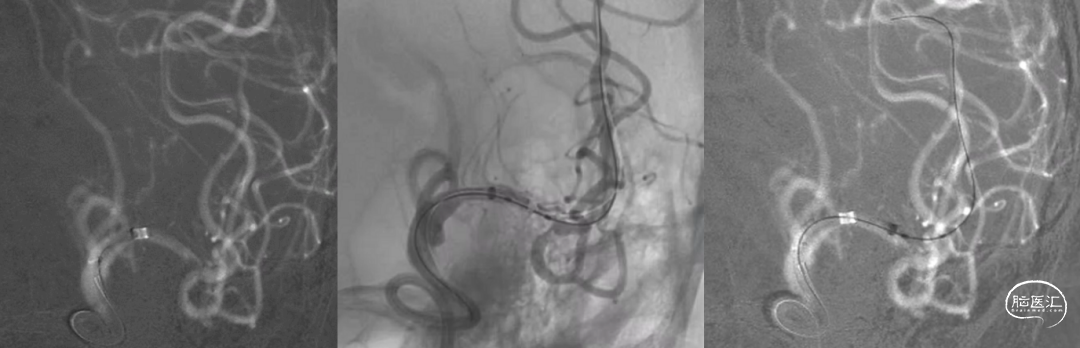

Synchro-14微导丝留置于左侧大脑中动脉下干远端分支建立轨道;沿导丝送入加奇SacSpeed® 2mm×9mm颅内球囊,造影定位于狭窄段。

加奇SacSpeed® 2mm×9mm颅内球囊缓慢充盈成形扩张原位狭窄段;经球扩后,责任病变血管狭窄程度明显改善,前向血运流速改善。

责任病变血管管壁毛糙,内膜撕裂?血栓附壁?

欣维宁10ml静脉推注、6ml/h泵注20min,使用Wingspan 2.5mm×15mm颅内动脉支架定位于残余狭窄段释放。

推送加奇SacSpeed® 2mm×9mm颅内球囊至支架内后扩张成形(加奇SacSpeed® 2mm×9mm颅内球囊内加压至12atm)。

最后造影显示支架贴壁良好、支架内血运通畅、支架以远各级动脉分支显影良好。